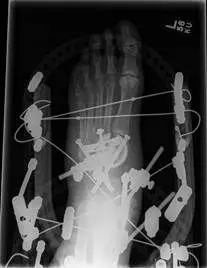

The condition easily progresses to a point where the foot is collapsed and pressure points present themselves in the center of the foot where the foot collapsed, predisposing the individual to pressure wounds also due in part to the lack of sensation. When this occurs the wound must be healed with wound care in conjunction with off-loading of the area with one of the above-mentioned devices. The final step in treatment would be surgical reconstruction of the foot or ankle, which in most cases involves both internal fixation of the bones and external fixation with a frame (pictured below).

Below are images of Charcot deformity in the midfoot and reconstructive surgery involving an external fixator, which is the metallic structure that you see outside of the area of the foot and leg with pins inserted into the foot and leg to allow support and reduction of the deformity to allow healing.